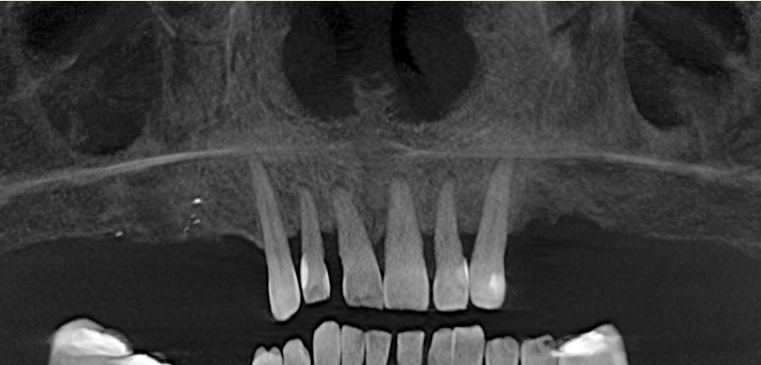

Ošetření horní bezzubé čelisti implantáty a fixním můstkem na čtyřech implantátech (all on 4)